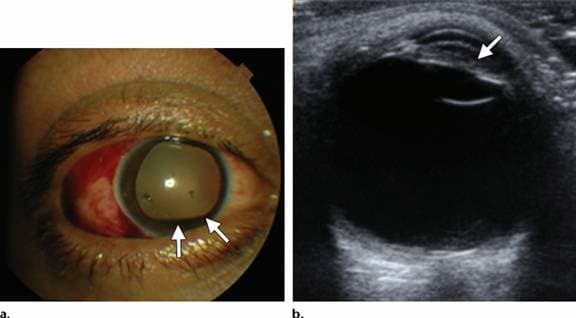

Khi thực hiện siêu âm A-Scan, nếu thấy có bất kì vấn đề gì bất thường như có dấu hiệu mắc đục thủy tinh thể hoặc không quan sát rõ phía sau của mắt, bác sĩ sẽ chỉ định siêu âm B-Scan. Đây là bước siêu âm quan trọng giúp quan sát rõ ràng không gian phía sau mắt. Đồng thời, thông qua siêu âm B-Scan, bác sĩ có thể chẩn đoán được mức độ lan rộng của khối u, bong võng mạc hoặc các bệnh lý về mắt khác.